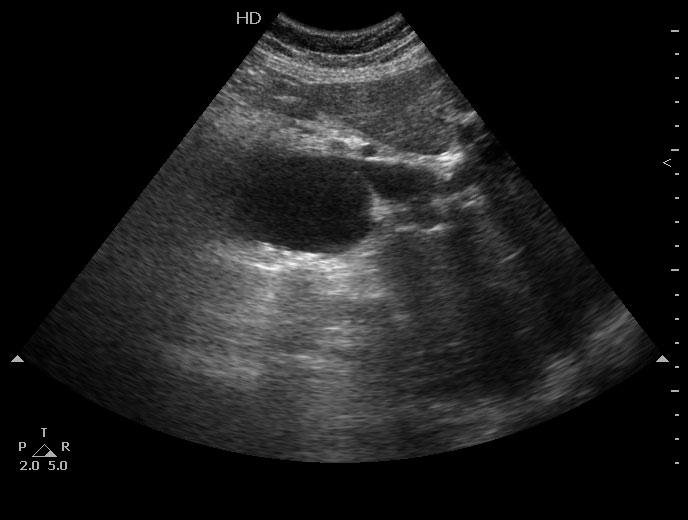

Добавлю сонограмму.